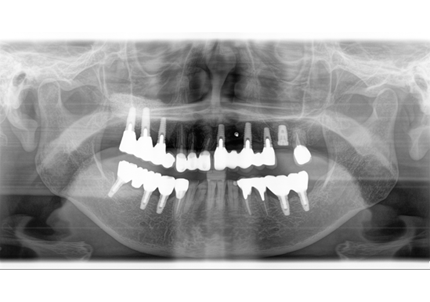

24.パノラマレントゲン

↑2006年4月24日(初診時)

↑2024年6月26日

25.初診より18年経過(2024年6月26日)